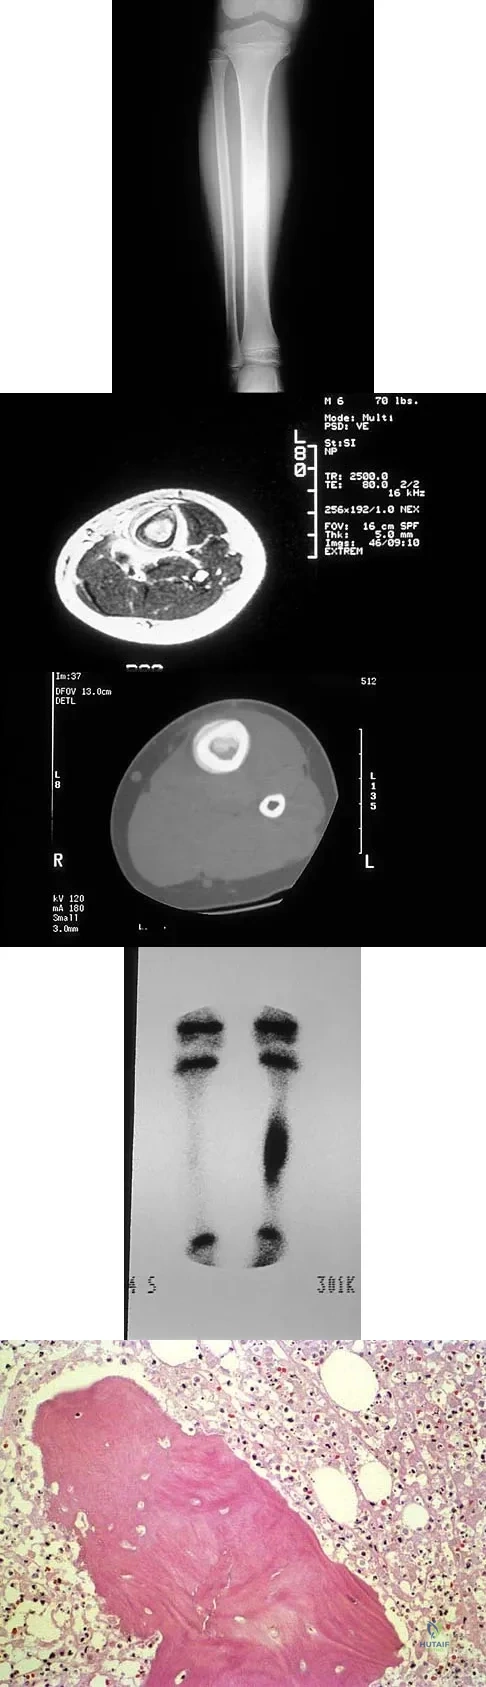

A 6-year-old boy has leg pain. A radiograph, MRI, CT, and bone scans, and a biopsy specimen are shown in Figures 14a through 14e. What is the most likely diagnosis?

Explanation